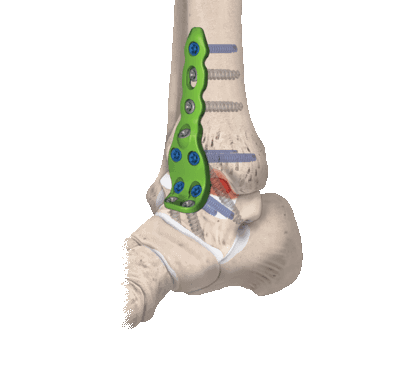

Отрывные переломы наружной лодыжки фиксируюттак, как показано на рисунках 14.8а, Ь. Используют треть-трубчатую пластину или стягивание проволокой.

А Короткий косой перелом малоберцовой кости фиксирован 3,5-мм кортикальным стягивающим шурупом. Эта фиксация дополнена треть-трубчатой пластиной, выполняющей функцию нейтрализационной пластины.

B,C,D Различные методы внутренней фиксации латеральной лодыжки при разных видах переломов.

D Наложение треть-трубчатой «противоскользящей» пластины сзади по Weber,

Операцию начинают с экспозиции перелома диафиза малоберцовой кости. Обязательным является точное восстановление длины малоберцовой кости. Перелом диафиза репони-руют и фиксируют при помощи одних лишь стягивающих шурупов или, гораздо чаще, сочетая их с треть-трубчатой пластиной.